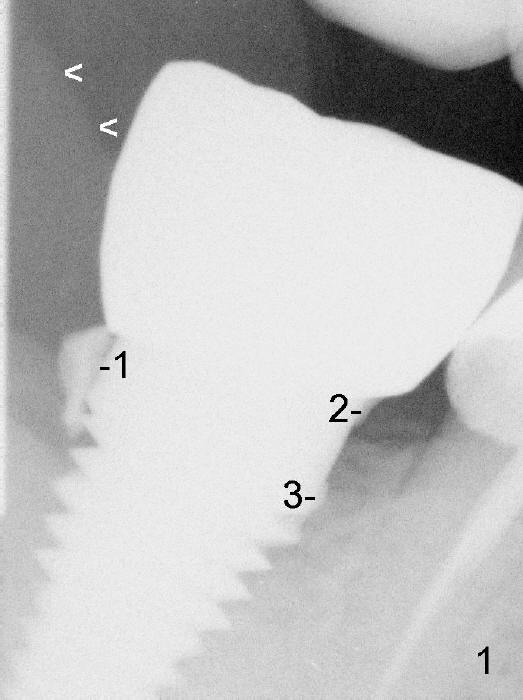

Four months post implantation, a Zirconia crown is cemented with Temp Bond. Two months later, the patient returns for recall. Bitewing shows 3 pieces of residual cement (Fig.1: #1,2,3) . Due to the thick distal gingiva (Fig.1 <), initial effort results in partial removal of the distal cement (Fig.2 (PA): #1). The shallow cement in the mesial aspect is apparently removed, whereas the deep one remains untouched (Fig.2: #3). Further removal is done before discharge without X-ray confirmation.